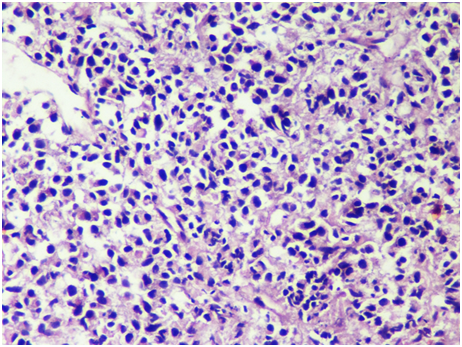

Fine needle aspiration cytology was performed which showed singly scattered monotonous population of atypical cells with high nuclear to cytoplasmic ratio. Few populations of cells revealed the bi‒nucleated forms with eccentrically placed nucleus, prominent nucleoli and basophilic cytoplasm (Figure 2). With mere cytology, it was difficult to give a definitive diagnosis so it was labelled as a small round blue cell tumor (SRBCT) with the differential diagnoses of Non‒Hodgkin’s Lymphoma, Plasma Cell neoplasm, Osteosarcoma and poorly differentiated metastatic carcinoma. Biopsy was advised for further evaluation. Tru‒cut biopsy showed diffuse sheet of monotonous population of dark blue round cells, few with eccentrically placed nucleus and eosinophilic cytoplasm. Bi‒nucleated forms were seen. This morphology was similar to cytomorphologic study done before (Figure 3). Further workups with hematologic studies, biochemical investigations and immunohistochemistry were performed to settle the diagnostic dilemma.

Figure 3H & E Section shows atypical small round blue cells in diffuse sheets, some with eccentrically placed nucleus and eosinophilic cytoplasm HPE (400X).